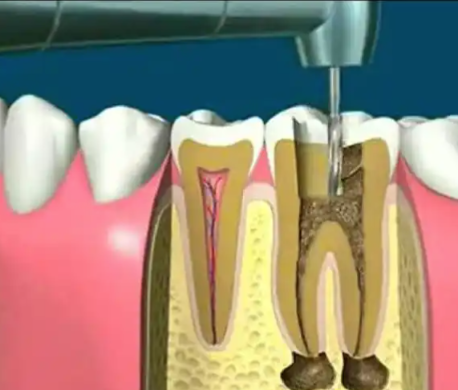

前牙美学修复与现代根管治疗:擅长前牙美学修复、贵金属烤瓷牙修复,同时可效率高完成各类牙髓病症的根管治疗,注重牙齿外观与功能的统一。